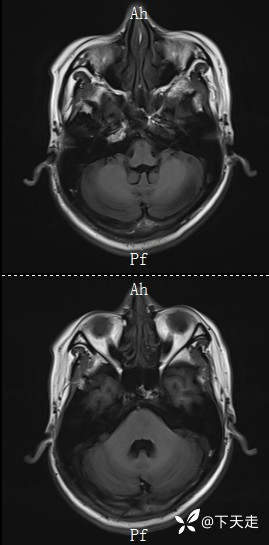

住院治疗第8天,夜间3点上厕所时感觉右侧肢体无力加重,未在意,继续卧床休息,7点肢体无力加重明显,右侧上下肢不能抬举,右侧下上肢2级。立即复查CT,排除脑出血,复查磁共振如下